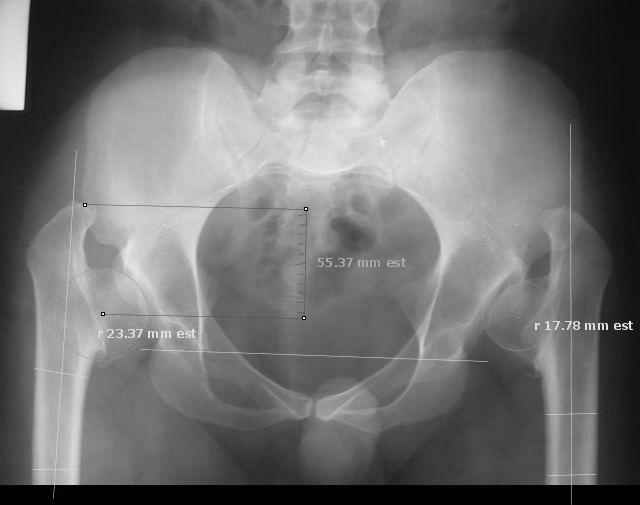

I took the liberty of 'marking up' your image with software tools we have been developing. Please note the measurements in millimeters are 'unscalled' because the image is not calibrated.

Derek Cooke